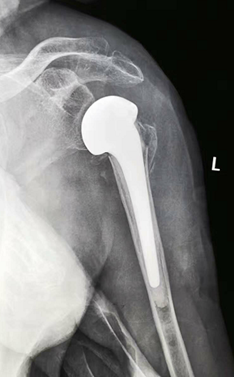

我科为国家中医药管理局“十二五”重点专科建设单位。拥有进口关节镜全套设备、髋膝肩肘人工关节置换全套体系、TDP治疗仪、电脑中频透热治疗仪、多功能微波治疗仪、中药煎药机、下肢功能锻炼机等诊疗设备。根据国内外关节外科发展方向,充分应用中医药发展优势,创立中西医结合特色。近年来已开展了髋、膝、肘、肩等关节人工置换术1000余例,每年各种关节置换100多例,各种关节镜微创手术、运动损伤致各种肌腱、韧带损伤修补重建手术200余例及各种关节骨折内固定手术近400余例,数量和质量居市内各大医院前列。本科室主持两项自治区科研课题两项,市科研6项,在国家杂志发表论文60余篇,研究了跌打散、郁金散、跌打郁金膏、驳骨膏、跌打追风酒、损伤外洗合剂等二十余种纯中药制剂,为满足患者术后快速康复需要,进一步开发了中药止痛贴、消肿贴、痛风贴等外用制剂,广泛运用临床。

①四肢骨关节疾患的人工关节置换及翻修治疗;

擅长中西医结合治疗骨科各种疑难疾病:骨质疏松、慢性腰腿痛、运动损伤、各种关节疾病、复杂关节内骨折、运动损伤、儿童骨骼发育异常等疾病。专长:髋、膝、肩等关节置换、翻修术,复杂关节骨折固定术、前后交叉韧带、半月板损伤、肩关节、踝关节等韧带重建微创手术。

擅长各种四肢骨关节疾病及运动创伤的治疗,各种四肢及复杂关节内骨折内固定术,尤其擅长各种人工关节置换术、翻修术及各种微创关节镜手术如膝关节交叉韧带重建、半月板损伤修复等治疗及基础、临床研究工作。

擅长各种髋、膝、肘、肩等人工关节置换术,各种复杂人工关节翻修术,各种脊柱疾病内固定手术,各种先天性关节畸形矫形术,复杂骨折内固定手术,骨关节疾病,运动创伤的关节镜诊断治疗技术。